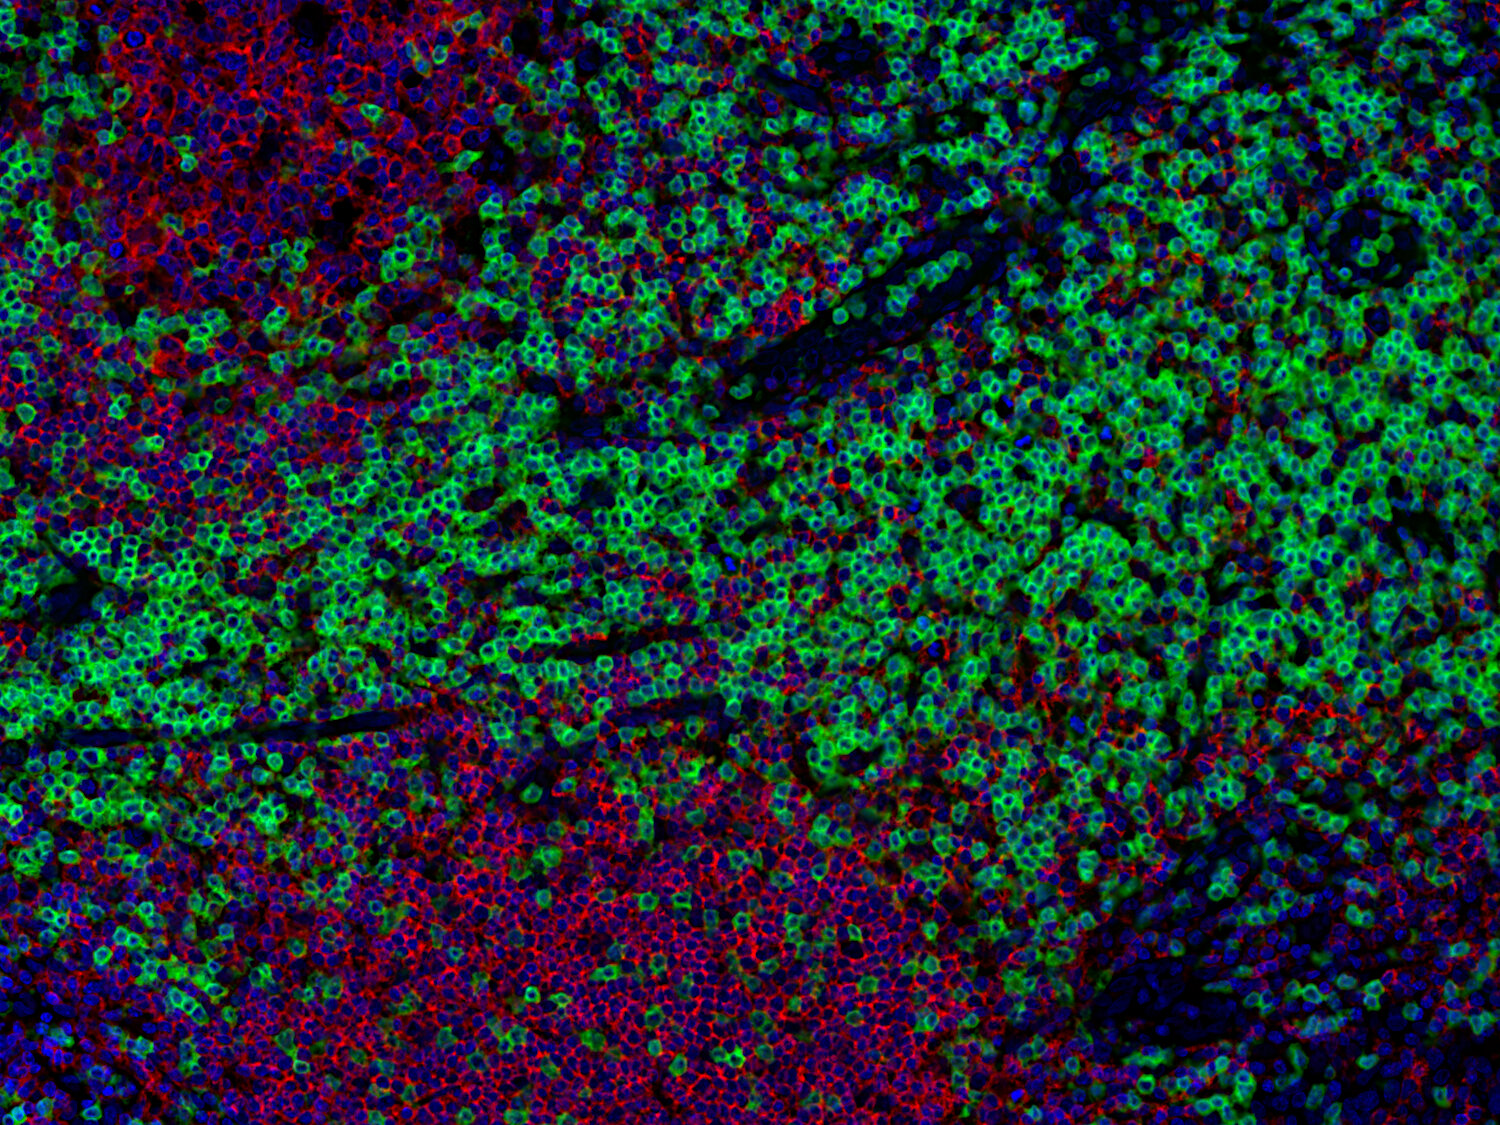

Immunofluorescence image of a human FFPE tonsil section stained for CD3e (T cells, green) and CD68 (macrophages, red)

Cluster of differentiation 3 (CD3) is a defining feature of cells belonging to the T cell lineage. It is composed of the four subunits CD3 gamma, CD3 delta, CD3 epsilon (CD3e) and CD3 zeta, that form a multimeric protein complex. This complex associates with the T cell receptor (TCR) and serves as a T cell co-receptor. The CD3 molecules contain immunoreceptor tyrosine-based activation motifs (ITAMs) that serve as the nucleating point for the intracellular signal transduction machinery upon TCR engagement. TCR/CD3 signaling is central to the initiation of antigen-specific T cell responses to pathogens and vaccines, as well as transplanted tissues, tumors, and autoantigens. CD3 is initially expressed in the cytoplasm of pro-thymocytes. During T cell maturation the expression of CD3 migrates to the cell-membrane. The specific appearance at all stages of T cell development make CD3 a useful immunohistochemical marker for T cells in tissue sections. In the clinical setting, CD3 is a relevant marker for the classification of malignant lymphomas and leukemias as the antigen remains present in almost all T-cell lymphomas and leukemias. It can also be used to detect T cells in celiac disease, lymphocytic and collagenous colitis.